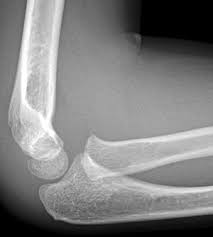

Cóndilo:

Protuberancia redondeada en el extremo de un hueso, que se encaja en el hueco de otro hueso formando una articulación.